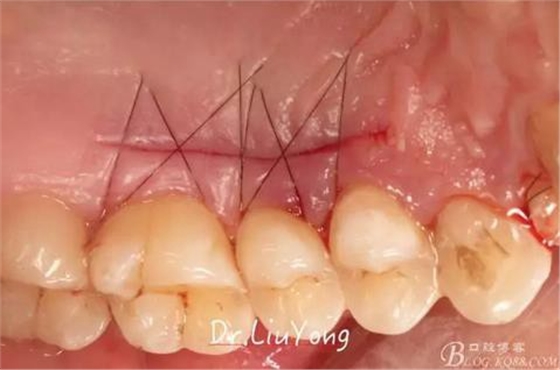

將結締組織瓣縫合固定于受區(qū),如上圖